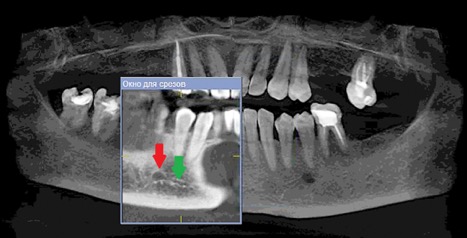

Данные осложнения происходят из-за повреждения резцовой петли – внутрикостного продолжения нижнелуночкого нерва (Рис. 1a и 1b), которая начинается от ментального отверстия и заканчивается индивидуально, как правило, на уровне латерального или центрального резца [1].

Рисунок 1а: КЛКТ. Панорамный реформат.

(Зеленая стрелка – резцовая петля, красная стрелка – подбородочное отверстие.)

Рисунок 1b- КЛКТ. Коронарныи реформат нижнеи челюсти в переднем отделе. (Зеленая стрелка резцовая петля).jpg

Рисунок 1b: КЛКТ. Коронарный реформат нижней челюсти в переднем отделе.

(Зеленая стрелка – резцовая петля)